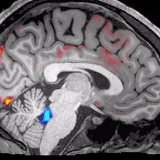

红色是血液,蓝色是脑脊液。厉害的是从前没有发现过,血液会周期性地大量流出大脑。每当血液大量流出,脑脊液就趁机发动一波攻击。脑脊液进入之后会清除毒素,比如导致阿尔茨海默病的β淀粉样蛋白。

当大量神经元一同停止了激发,就不需要那么多血液进去输送氧气,才给了脑脊液涌入的机会。这样,便有了我们在开头看到的那副景象: